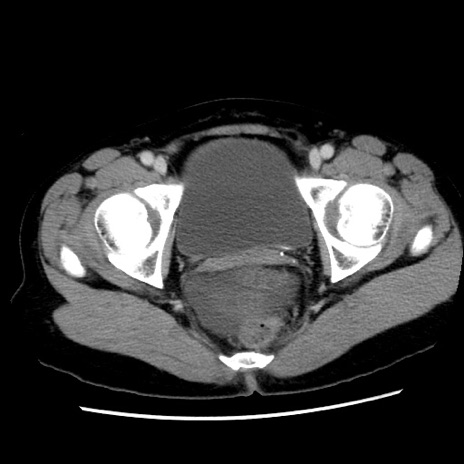

症例10(横断像)

【症例】 50歳代女性

【主訴】 腹痛

【現病歴】前日生レバーを食べた。今朝に排便あり。 昼前に突然発症の腹痛を生じ、当院救急外来を受診した。

【既往歴】 子宮筋腫にてで子宮全摘後

【身体所見】 意識清明、腹部:平坦、軟、下腹部やや左を中心に圧痛・反跳痛あり、筋性防御あり

【データ】WBC 7800、CRP 0.07